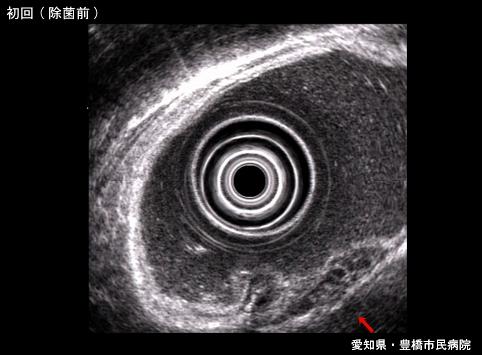

放射线疗法有效的胃MALT(粘膜联结淋巴组织mucosa associated lymphoid tissue)淋巴瘤(病例提供:爱知县, 丰桥市民病院, Dr. 后藤)

[ Image ID:6431 ]

疾病(病理主体)的分类

恶性淋巴系肿瘤/恶性淋巴瘤

部位(按器官分)

胃(部位)/体部

检查方法

超声波

肿瘤的肉眼分类

0型(表在型)/IIa型(IIa+IIc)

肿瘤最大直径